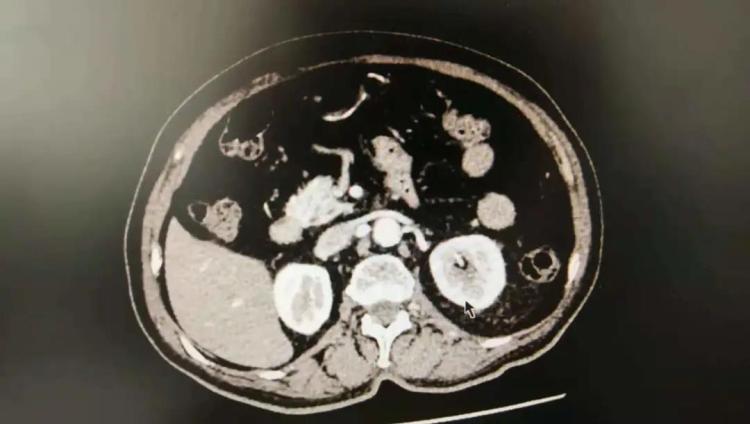

今年75岁的孙先生患高血压多年,血压控制尚可。但近半年,他口服3种降压药血压仍达190/110mmHg左右,同时出现尿中泡沫,有头痛及腰疼等表现。入住市中心医院老年医学科高血压病房后,除常规筛查继发性高血压各项指标外,医院还给予孙先生肾、肾上腺、肾动脉CTA检查。结果,检查提示孙先生双侧肾动脉起始部管腔中重度狭窄。随后行肾核素显像评价肾功能,提示他左肾功能大致正常,右肾功能轻度受损。

结合临床,医生考虑孙先生为肾血管性高血压,转血管外科行肾动脉造影检查,提示双侧肾动脉起始部80%-90%重度狭窄,各放置支架一枚。术后当天,孙先生血压便降至124/74mmHg,术后未口服任何降压药血压维持在大致正常范围内。目前,孙先生已治愈出院。